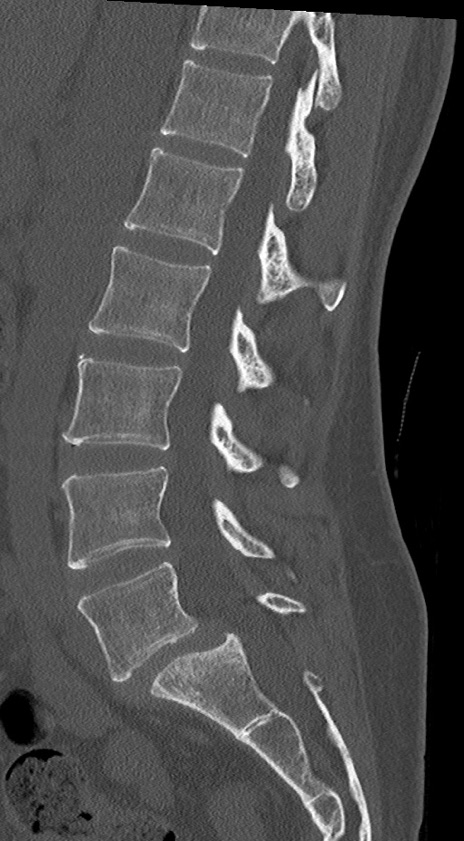

【整形】TIPS症例4 腰椎CT(矢状断像)

腰椎CT

冠状断像